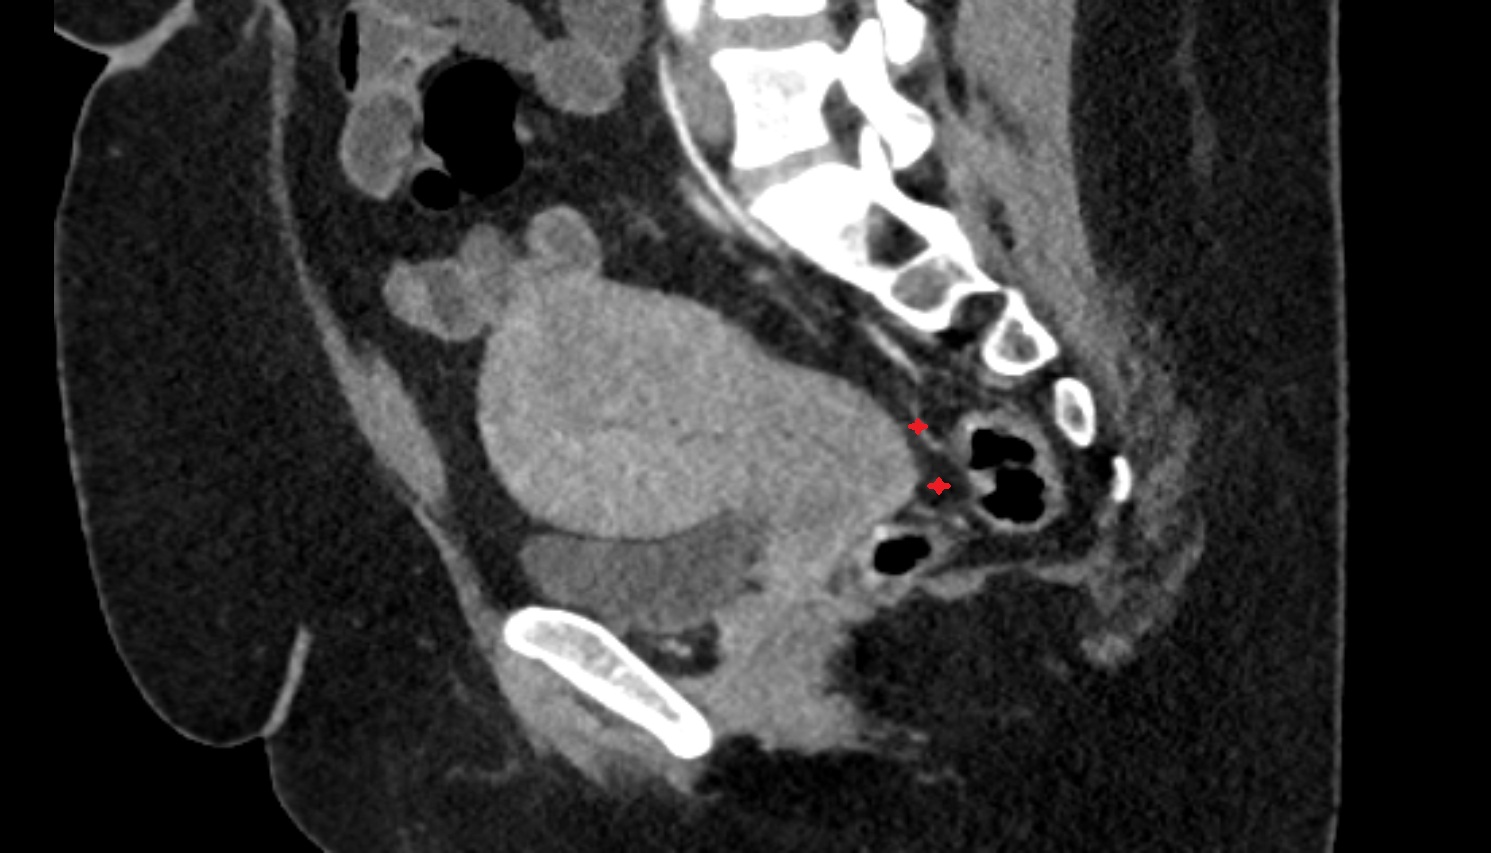

- Uterus

- Cervix of uterus

- Vagina

- Rectouterine pouch (pouch of Douglas)